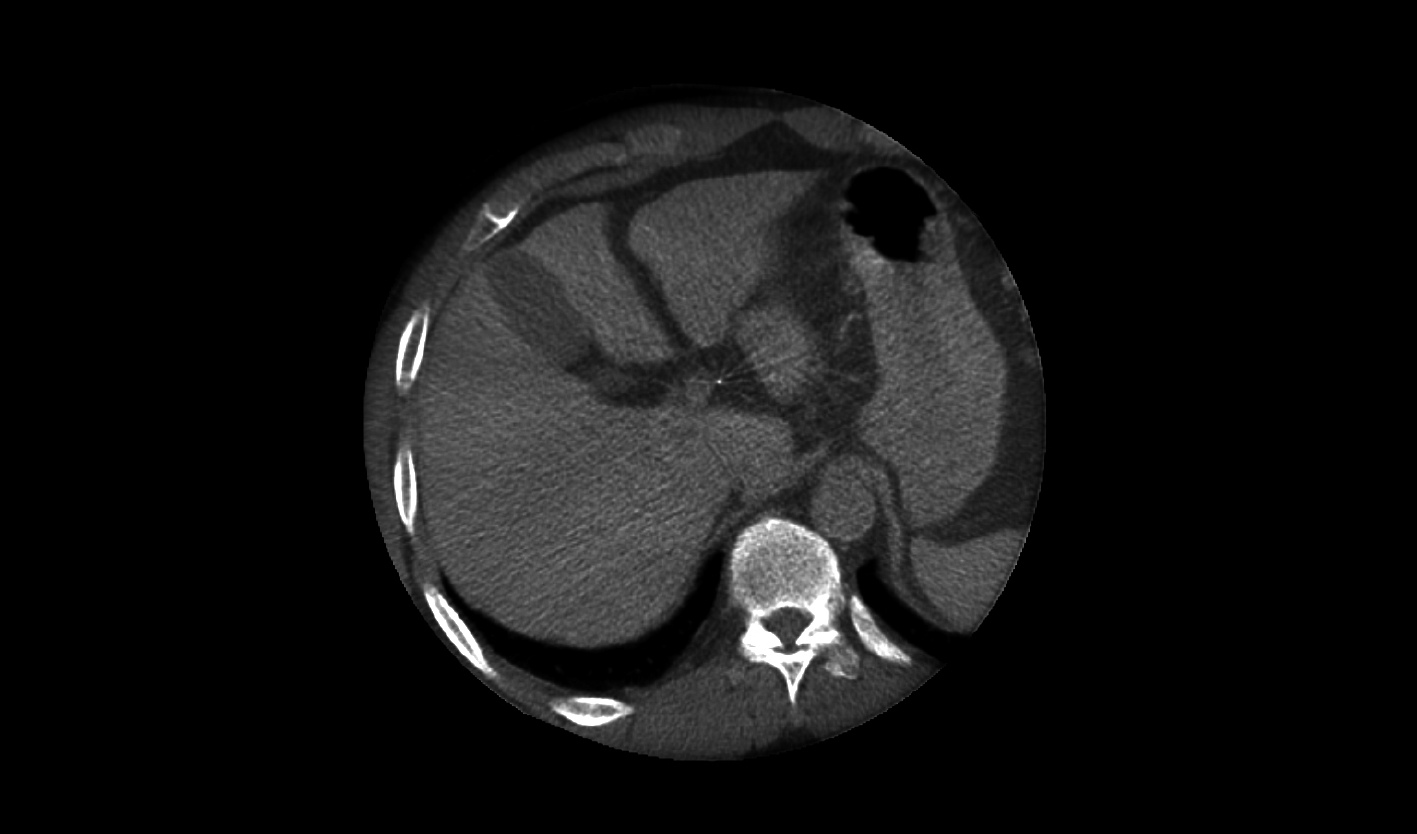

辽阔视野

*40×30cm成像面积,大部位成像一次性覆盖